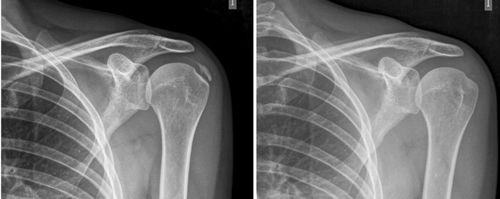

Figura 1

Figura 2

Tabla I

Figura 3

Figura 4

Figura 5

Figura 6